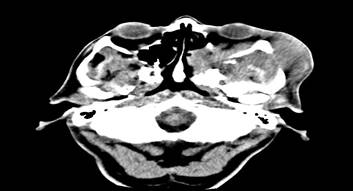

La TAC evidenció masa heterogénea a nivel del seno maxilar, destrucción ósea de la pared lateral del seno, piso de la órbita y arco cigomático, además se observó extensión hacia partes blandas de la región temporo-parietal izquierda (Figura 3 y 4).

Las imágenes de seno maxilar ocupado por masa de aspecto tumoral con compromiso de estructuras óseas vecinas (observadas en la TAC) y el análisis histológico fueron determinantes para el diagnóstico de carcinoma epidermoide de seno maxilar. Llegar a este resultado por lo general es tardío porque los signos y síntomas son inespecíficos. La relación de proximidad del seno maxilar con la base de cráneo, órbita, cavidad nasal, seno esfenoidal, seno etmoidal y el frontal hacen que la planificación del tratamiento sea compleja.